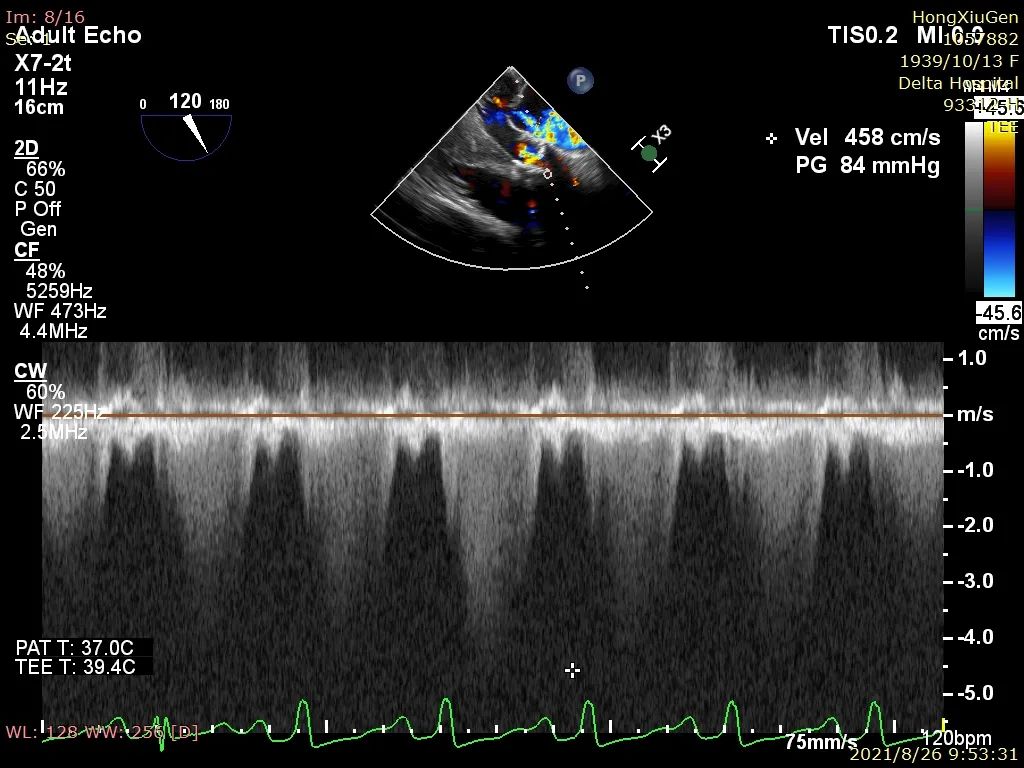

入院行相关辅助检查后,心电图示“窦性心动过速;S-T段变化;左心室高电压”;心脏彩超示“主动脉瓣狭窄(重度)伴关闭不全(轻度)、峰值流速450cm/s、平均压差46mmHg、估测主动脉瓣开放面积0.7cm²;二尖瓣关闭不全(轻中度),三尖瓣少量反流,左室收缩功能减低;LVEF:36%”。

4、180次/分快速起搏下以22mm 球囊进行第一次预扩张,扩张同时造影示明显腰征,球囊受挤压上跳。扩张后超声示跨瓣压差37mmHg,峰值流速303cm/s,主动脉狭窄情况得到改善,主动脉瓣叶活动性增强;